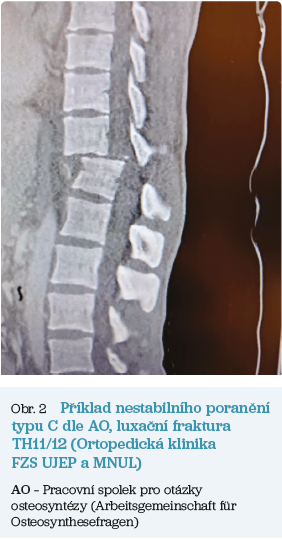

Obr. 2 Příklad nestabilního poraněníU vysokoenergetických traumat či v rámci polytrauma protokolu je automaticky provedeno spirální CT vyšetření hlavy a trupu, které odhalí většinu možných poranění páteře.

U nízkoenergetických poranění je nejprve zjištěno podezření na zlomeninu na provedeném rentgenovém snímku a poté následuje CT vyšetření.

Indikace magnetické rezonance (MR) v případě akutního traumatu páteře je kontroverzní. Některá pracoviště provádějí MR vždy při poranění s neurodeficitem. Nevýhodou MR je delší doba vyšetření, což může oddalovat provedení léčebného operačního výkonu. U těžce traumatizovaných pacientů může být provedení MR vyšetření komplikovanější z důvodu možné přítomnosti kovových feromagnetických fixačních materiálů či nutnosti monitorace nestabilního pacienta. Naproti tomu benefitem MR oproti CT vyšetření je odhalení hemoragie, traumatické hernie disku či verifikace ligamentózního poranění.